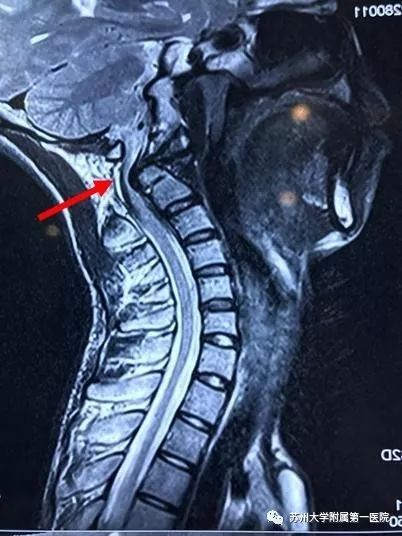

磁共振显示高位颈髓严重受压

图片尺寸402x536